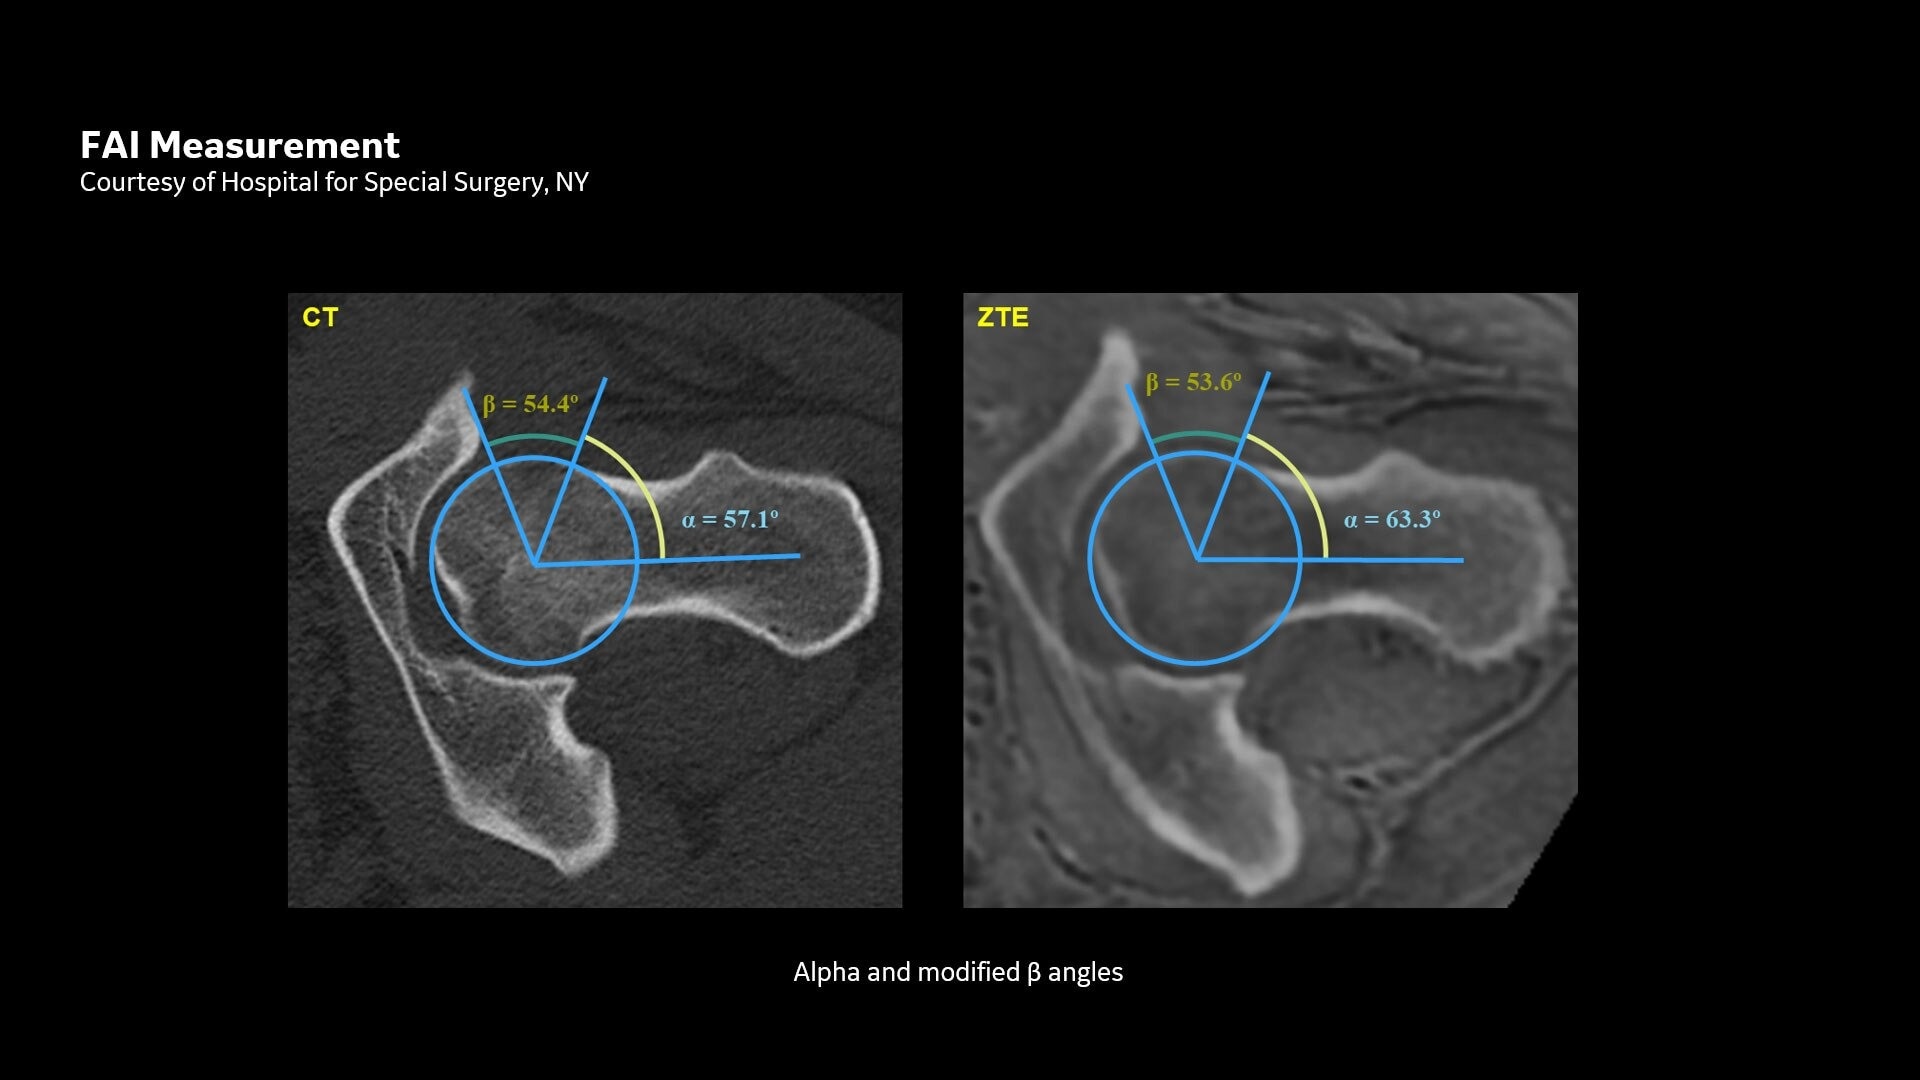

Available for all anatomies without ionizing radiation, oZTEo delivers images of bone morphology, calcification, ossification and fractures. oZTEo complements conventional MR soft tissue exams with perfect co-registration and provides 3D isotropic imaging using a radial ZTE acquisition, with inherent motion insensitivity. Use oZTEo with Volume Illumination for realistic 3D rendering.